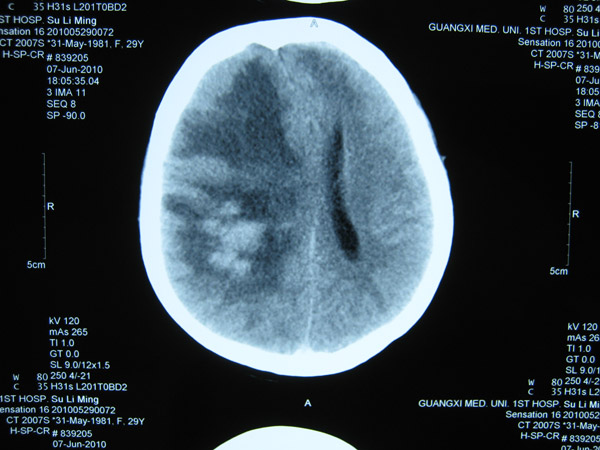

2011年5月1日,覃某顺产1名女婴后出现发作性意识障碍,伴双目上视,伴牙关紧闭、口吐白沫、四肢抽搐、二便失禁,醒后伴头晕、四肢乏力、左侧肢体麻木等不适症状,遂到当地医院就诊。在其住院过程中出现意识障碍伴左侧肢体活动障碍、左下肢肿胀等症状,在进行头颅MRI+MRA等检查后,覃某被当地医院诊断为“颅内静脉窦血栓形成并伴脑皮质出血、症状性癫痫、左下肢静脉血栓形成”。

头颅CT2